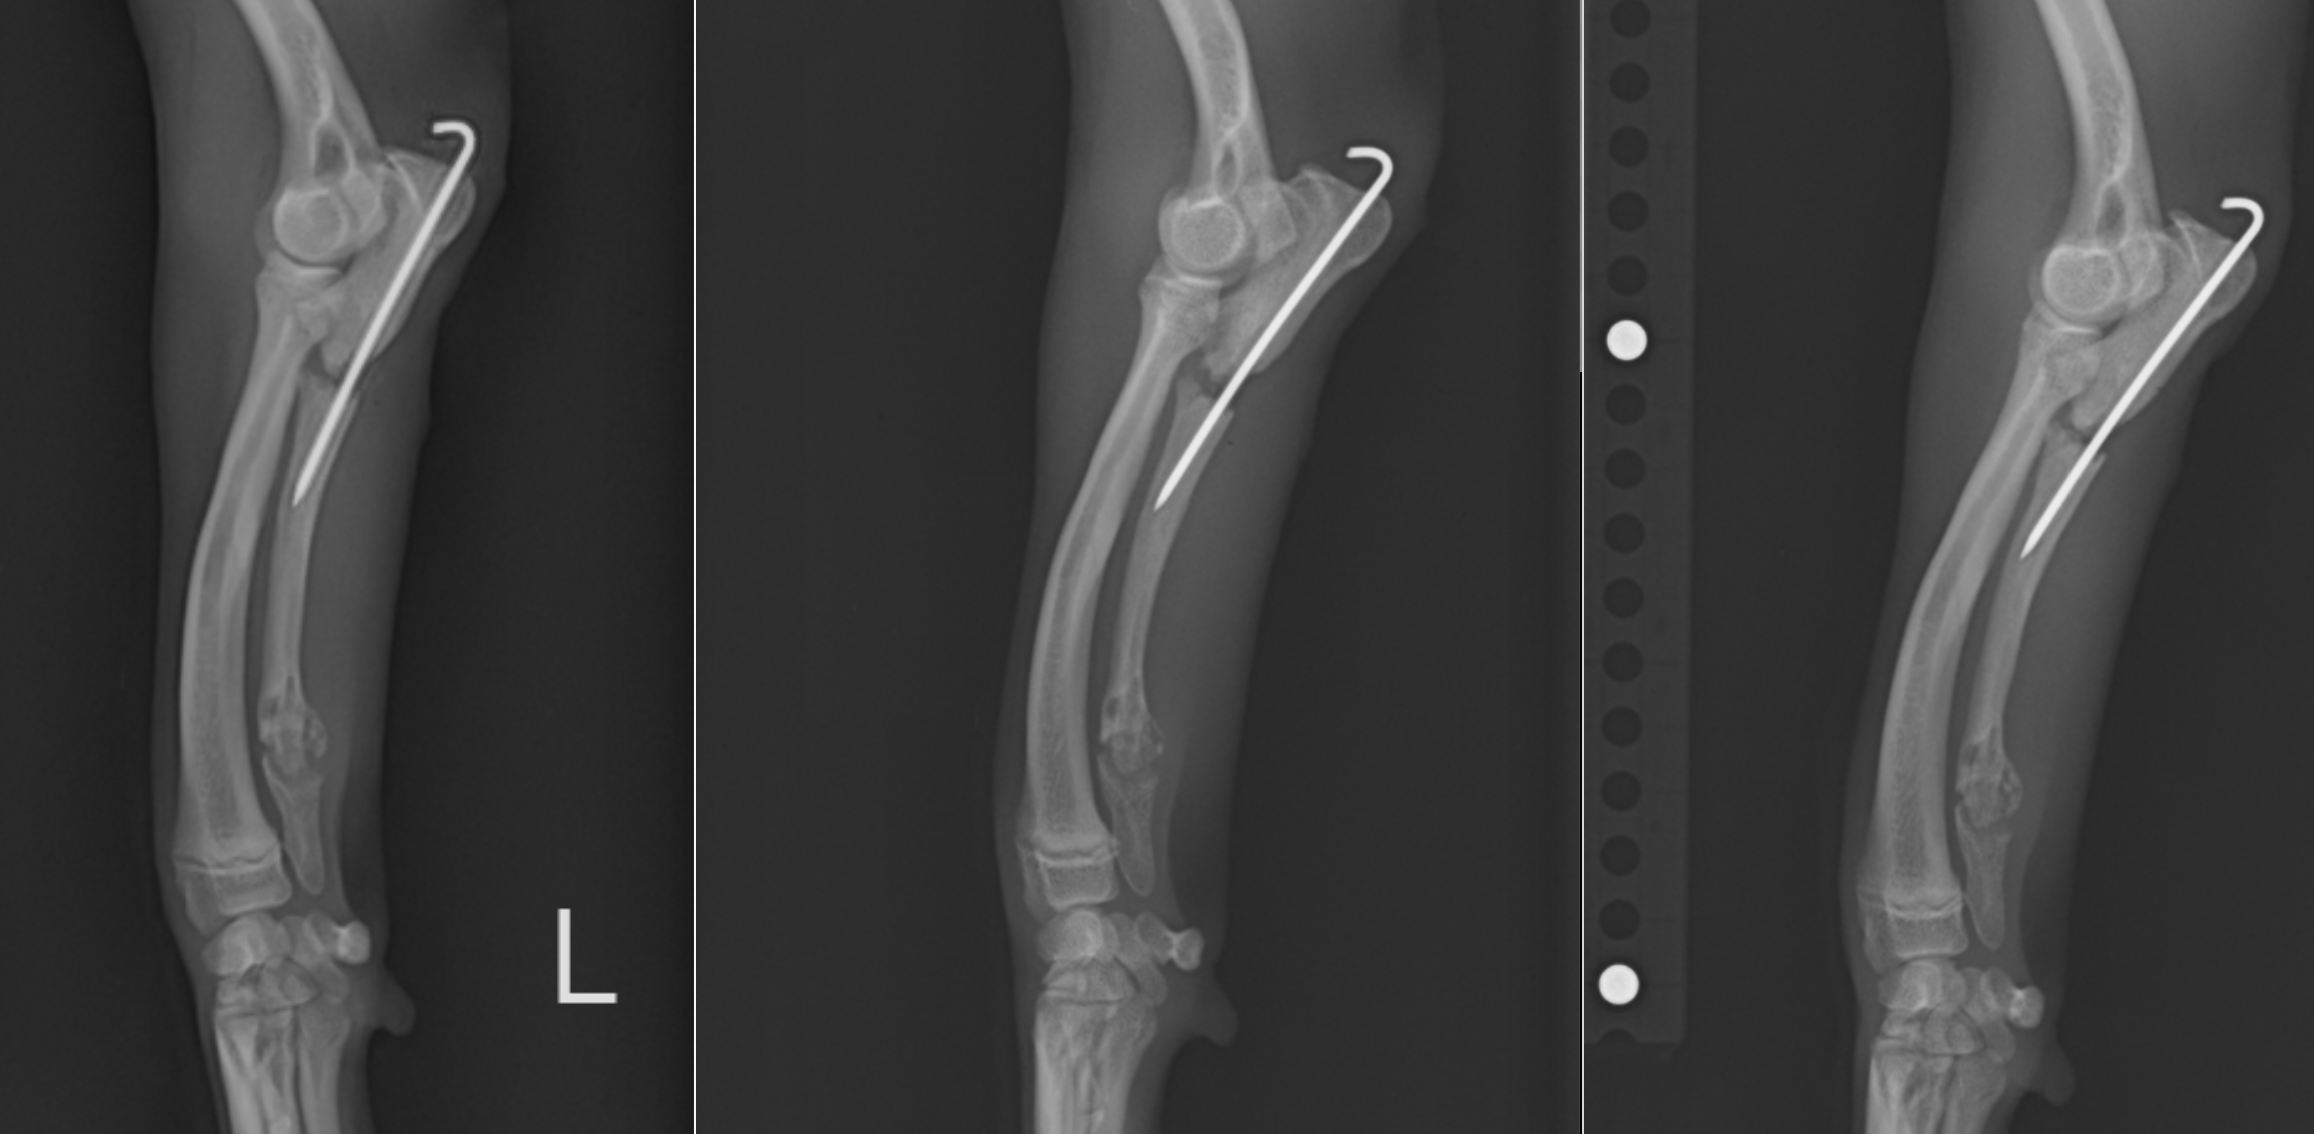

術後のレントゲンです。黄色が尺骨の関節部分、青色が上腕骨の骨を指していますが、一番左の術前ではその間隔が広いのが分かると思います。術後少しその間隔が短くなっており(真ん中)、術後2週間ではさらに短縮され、肘が正常に近づいているのが分かると思います。

さらに時間が立つと、離れた骨の間に骨が形成され、骨が癒合していきます。癒合した段階でピンを抜去していきます。